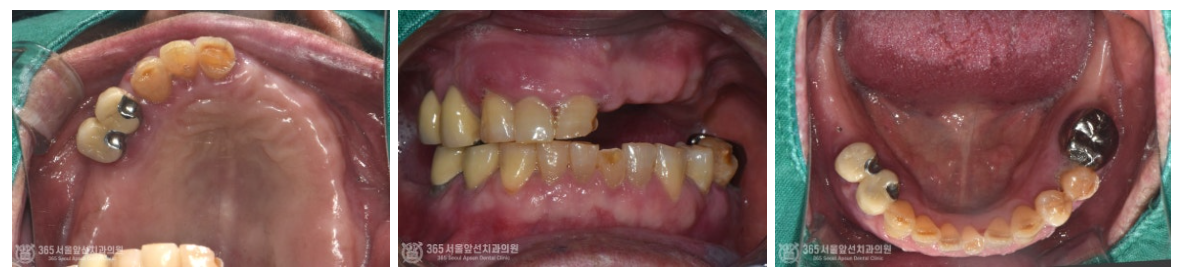

촬영일시 : 24.06.12 구강 내 모습입니다. 과거에 틀니를 사용하셨던 흔적이 관찰됩니다.